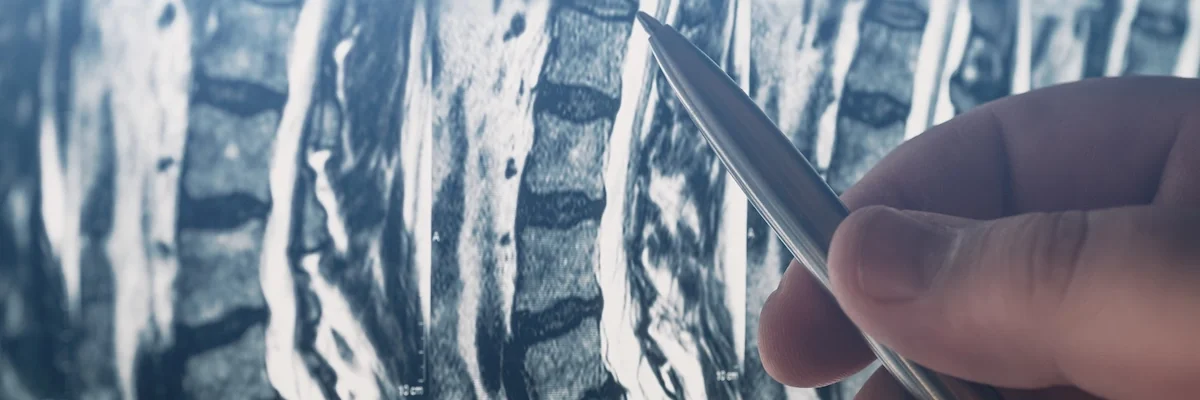

Degenerative Disc.

Arthritis.

Stenosis.